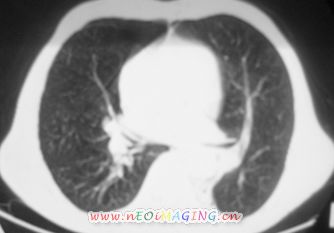

以下是引用卜一在2007-10-7 9:38:00的发言:[br]左下肺胸膜下团片影,内见含气支气管像,临近胸膜未见增厚。多考虑:1 左下肺炎症,建议消炎后复查!2 不除外肺隔离症合并感染!